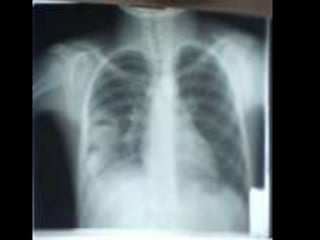

• • • • • • • • • • C’est un téléthoraxde face objectivant une volumineuse opacité de tonalité hydrique hilaire gauche Forme : grossièrement ovalaire Taille : mesure 6 à 8 cm de grand axe Limites : interne noyée dans le médiastin et se raccordant à angle aigue avec le bord gauche du médiastin. Limite externe flou irrégulière réalisant l’aspect en patte de crabe Plage : hétérogène par la présence de broncho gramme aérien Index cardio thoracique, les culs de sacs pleuraux sont libres On note une petite opacité de tonalité calcique se projetant sur le lobe supérieur du poumon droit Conclusion : gros hile tumorale malin gauche évoquant un cancer bronchique proximal Pas de diagnostic différentiel CAT : bilan d’extension:fibroscopie bronchique, TDM thoracoabdominale, échographie abdomino-pelvienne et scintigraphie osseuse